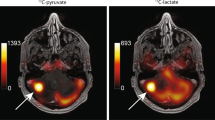

Radiation necrosis was initiated by employing a CT-guided 80-Gy single-dose irradiation of a half cerebrum in mice (n = 7). Intracerebral tumor was modeled with two orthotopic mouse models: GL261 glioma (n = 6) and Lewis lung carcinoma (LLC) metastasis (n = 7). 13C 3D MR spectroscopic imaging data were acquired following hyperpolarized [1-13C]pyruvate injection approximately 89 and 14 days after treatment for irradiated and tumor-bearing mice, respectively. The ratio of lactate to pyruvate (Lac/Pyr), normalized lactate, and pyruvate in contrast-enhancing lesion was compared between the radiation-induced necrosis and brain tumors. Histopathological analysis was performed from resected brains.

Conventional MRI exhibited typical radiographic features of radiation necrosis and brain tumor with large areas of contrast enhancement and T2 hyperintensity in all animals. Normalized lactate in radiation necrosis (0.10) was significantly lower than that in glioma (0.26, P = .004) and LLC metastatic tissue (0.25, P = .00007). Similarly, Lac/Pyr in radiation necrosis (0.18) was significantly lower than that in glioma (0.55, P = .00008) and LLC metastasis (0.46, P = .000008). These results were consistent with histological findings where tumor-bearing brains were highly cellular, while irradiated brains exhibited pathological markers consistent with reparative changes from radiation necrosis.

Hyperpolarized 13C MR metabolic imaging of pyruvate is a noninvasive imaging method that differentiates between radiation necrosis and brain tumors, providing a groundwork for further clinical investigation and translation for the improved management of patients with brain tumors.